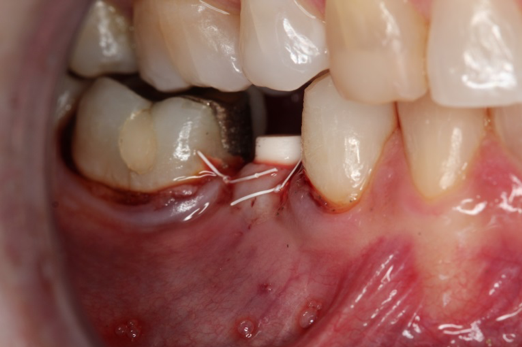

Fig 20. Immediately after extraction and placement.

Figure 20

Fig 21. Retainer provisional.

Figure 21

Occasionally dentists are presented with extreme challenges with long-term restorations and replacing missing teeth. Dentists must evaluate the patient's condition, develop optimum long-term oral health, and attempt to meet the patient's expectations. Figure 18 showed a class III malocclusion with deep bite, multiple abfractions, and less-than-ideal occlusal plane, but the patient wanted to replace his maxillary right canine only. A discussion with the patient regarding occlusal disharmonies and comprehensive recommendations for full-mouth rehabilitation revealed that the patient had a limited budget for dental care. The patient understood the ramifications of his comprehensive dental needs not being affordable. Decisions were made to atraumatically remove the maxillary right canine (Figure 19) and immediately place a ceramic dental implant (Figure 20). Polytetrafluoroethylene (PTFE) 4-0 sutures were placed to help support soft tissues, and then a full-arch Essix-style retainer with a flowable composite facial veneer was used to provide some esthetics during the patient's healing phase (Figure 21). The implant and the retainer were not to be in contactthe retainer may occlude with the opposing dentition and also be passive in relation to the ceramic implant.

Sutures were removed 2 weeks after surgical implant placement, and the patient was instructed to continuously wear his Essix-style retainer for 12 weeks. The retainer was worn while eating during the 12-week period. The patient returned at 12 weeks for soft-tissue and implant-bone evaluation (Figure 22). At this appointment, minimal lingual soft-tissue manipulation was performed by gingival abrasion to the keratinized soft tissue and an aluminum chloride gel was placed.